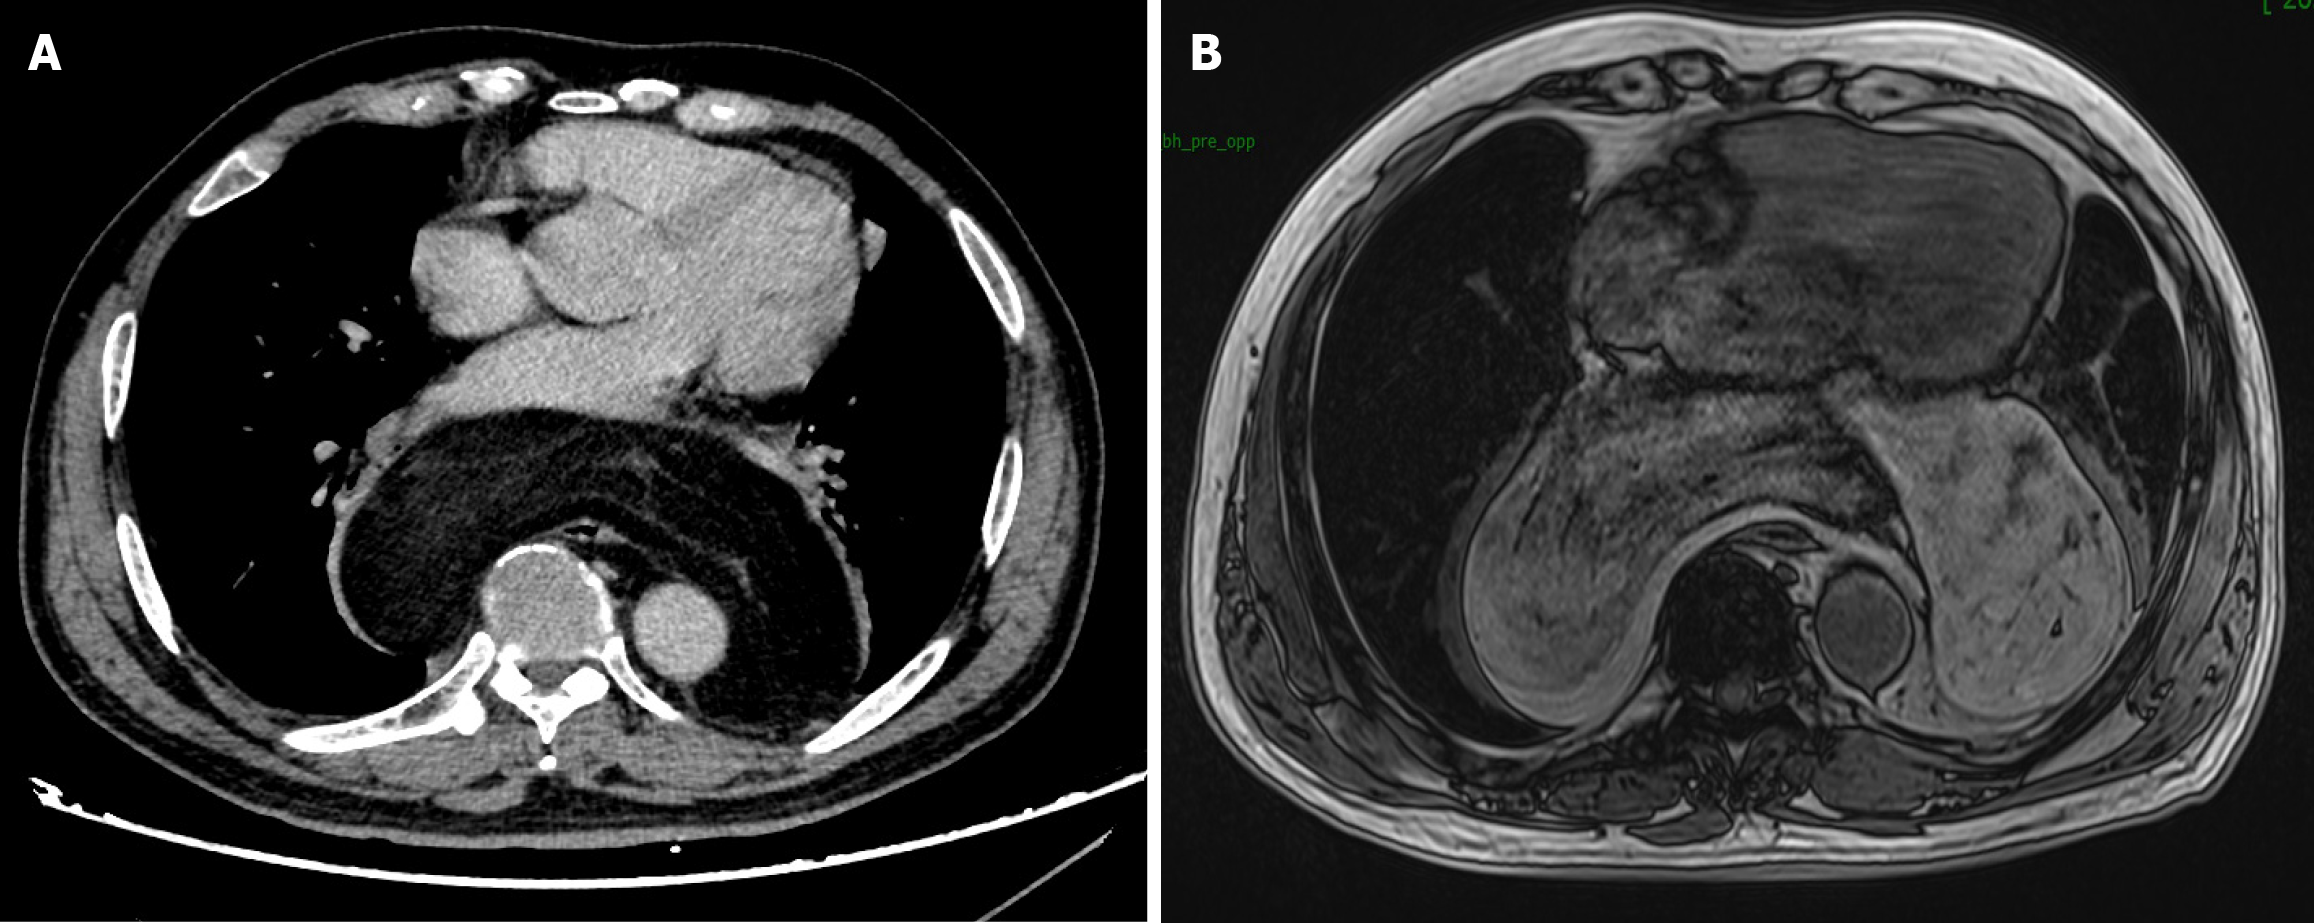

Figure 2 Surgical incisions for the bilateral single-port video-assisted thoracoscopic surgery.